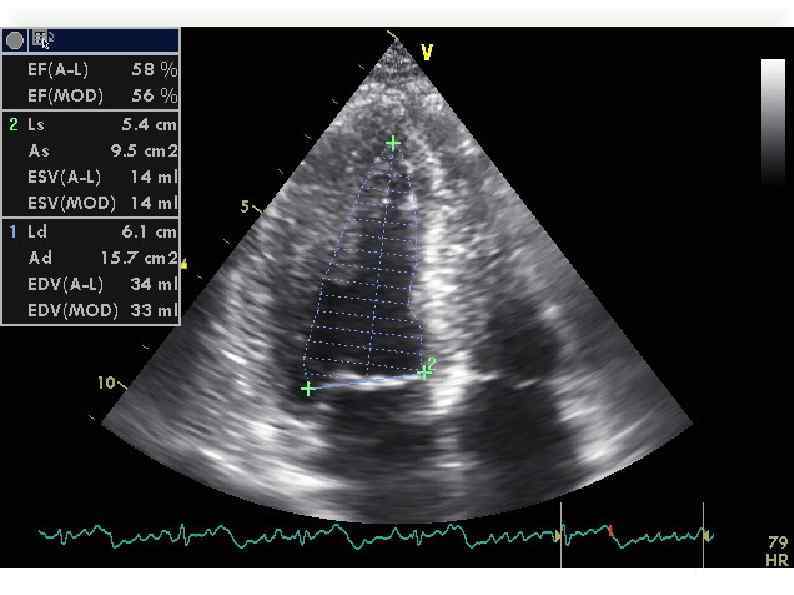

Эхо-КГ 21/09/11 Эхо-КГ 21/09/11

Эхо-кг 2/10/11 При сравнении с предыдущим исследованием отмечается заметная положительная динамика в виде уменьшения Эхо-кг 2/10/11 При сравнении с предыдущим исследованием отмечается заметная положительная динамика в виде уменьшения размеров левого желудочка и улучшения сократительной функции